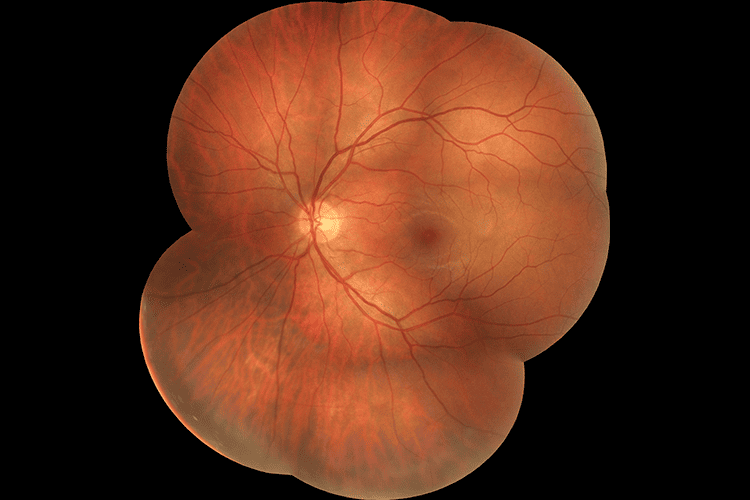

Вбудована в OCT-R1, ретинальна камера тепер є частиною оптичної системи, яка ще більше покращує якість отриманих зображень сітківки. Удосконалена технологія Canon EOS Retina, інтегрована в OCT-R1, покращує діагностичні можливості та результати для пацієнтів завдяки функції повного автофокусування та зйомки при оптимізованому спостереженні за світлом та інтенсивністю спалаху.

Технологія Canon Opacity Suppression

Цей унікальний і складний програмний інструмент відновлює початкову яскравість і колір сітківки. Технологія зменшує несприятливий вплив помутнінь очей, таких як катаракта, для більш чіткого перегляду кровоносних судин, що призводить до того, що незрозумілі структури стають більш впізнаваними.